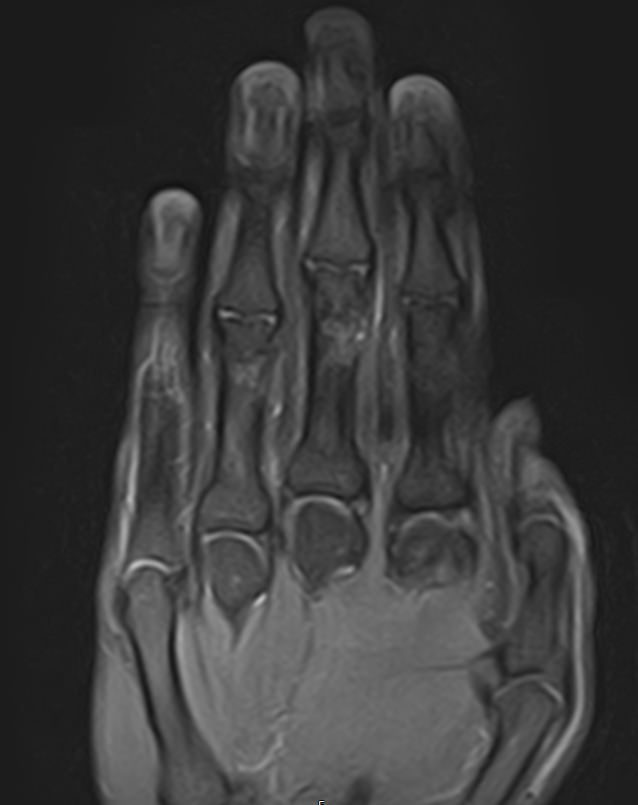

Современным и высокоточным методом диагностики заболеваний кистей рук является магнитно-резонансная томография. МРТ дает наиболее полную информацию о состоянии костей, суставов, связок, сухожилий, нервных волокон и мягких тканей кисти. Дополнительным преимуществом МРТ является ее безопасность, так как в основе метода лежит использование внешнего магнитного поля без применения ионизирующего излучения. При необходимости это позволяет выполнять исследование неоднократно в течение короткого периода времени.

Клиника «Доступная медицина» располагает новейшим 32-канальным высокопольным томографом закрытого типа TOSHIBA VANTAGE TITAN 1,5 Тесла, который позволяет получать изображения зоны кистей рук с высокой степенью детализации. Данные, полученные по результатам МР томографии, дают возможность врачу поставить точный достоверный диагноз и назначить своевременное лечение.

МРТ кисти руки – это высокоспецифичный метод визуализации мышц, связок, хрящей, костного мозга, жировой ткани.

С его помощью обнаруживаются:

• деструктивные изменения в суставах;

• утолщение синовиальных оболочек, выстилающих суставные полости;

• воспалительные выпоты ;

• краевые дефекты костной ткани;

• растяжения, разрывы связок , сухожилий сгибателей — разгибателей;

• субхондральные кисты (деградация кости вокруг суставного хряща);

• доброкачественные новообразования мягких тканей пальцев кисти (нодулярный теносиневит, сухожильный ганглий);

• злокачественные опухоли (остеосаркомы, мягкотканные саркомы ).

МРТ сухожилий и мягких тканей кисти руки помогает с постановкой окончательного диагноза, установленного при помощи других методик.